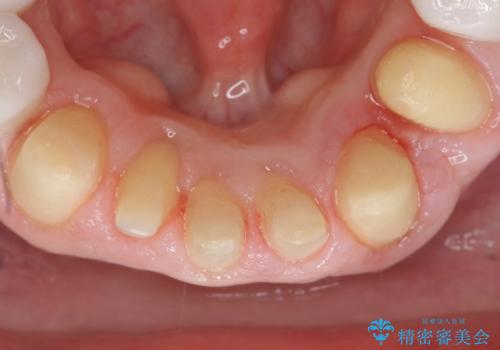

矯正治療とホワイトニングを提案しましたが希望されず、「接客関係の仕事で矯正治療は考えられない、短期間で治療を終わらせたい、ホワイトニングでは難しい位の人工的な白さにしたい」とのご要望により、治療前にワックスアップ模型を作製し何度もコンサルテーションを重ね、治療方針を決定しました。

歯頚ラインが変えられないことや天然歯を削るリスクをご理解頂いた上で、オールセラミッククラウンによる補綴治療を行いました。(見えない奥歯のみ天然歯のままとしました)

下の前歯1本だけ歯軸を変えるために神経をとり根管治療を行っております。

それ以外の歯は神経をとらずに済むよう、慎重かつ丁寧に歯の形態を整えました。